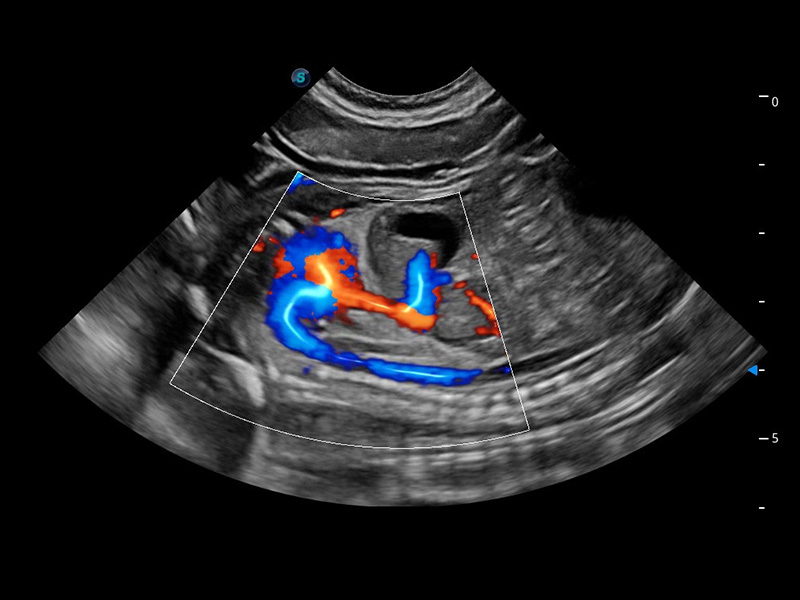

ProPet 60 作為一款高端臺(tái)式動(dòng)物超聲設(shè)備,為動(dòng)物醫(yī)生的日常診斷提供了一系列貼合動(dòng)物臨床需求、解決臨床實(shí)際問題的高級(jí)成像功能。憑借全系列高清探頭,滿足醫(yī)生對(duì)腹部、心臟、生殖、淺表、肌骨等成像的所有需求,切實(shí)幫助您提升檢查效率,提高診斷信心。